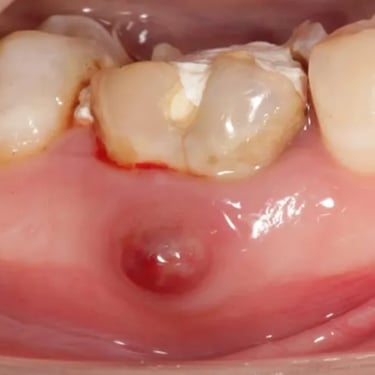

Absceso Periapical Agudo

Un absceso periapical agudo es una acumulación de pus en la punta de la raíz del diente debido a una infección.

Los pacientes suelen experimentar dolor intenso, hinchazón y fiebre.

Esta condición requiere tratamiento inmediato, como el drenaje del absceso y un tratamiento de conducto. Sin tratamiento, la infección puede propagarse a otras áreas.